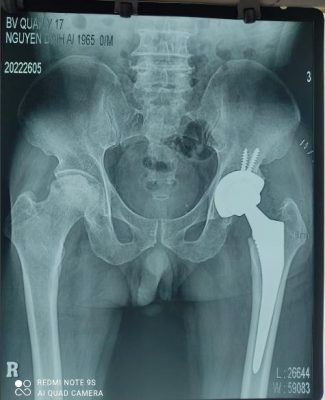

Thất bại sau kết xương gãy Thay khớp háng sau thất bại sau kết xương

liên mấu chuyển xương đùi gãy liên mấu chuyển xương đùi liên mấu chuyển xương đùi

- Thất bại sau phẫu thuật kết xương gãy cổ xương đùi, liên mấu chuyển xương đùi